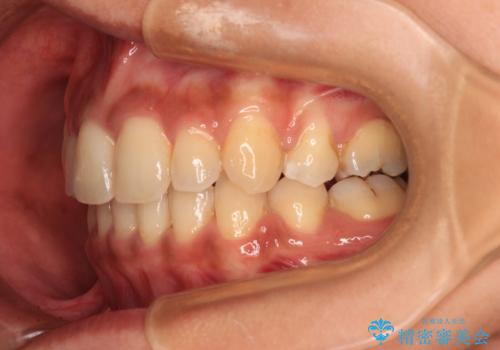

- 八重歯と上下前歯のでこぼこを気にして来院された患者様です。

上下前歯部叢生のスペース獲得のため、上下顎左右小臼歯各1歯(計4本)を抜歯して、ワイヤー装置にて矯正治療を行うこととしました。

上下の正中位置が大きくずれていたため、上下正中が合わないまま終了することが予想されましたが、思っていた以上にスムーズに歯が移動し、満足いただける仕上がりとなりました。